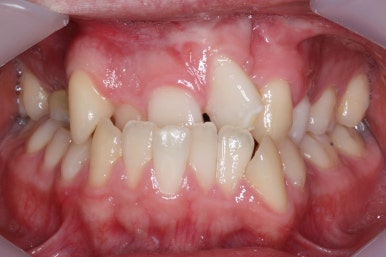

부산구순구개열 키다리아저씨치과에 처음 오셨을 때의 입 안의 모습입니다.

또한 위턱이 앞으로 자라나는 것도 방해해 대부분 앞니가 거꾸로 물리게 됩니다.

이번 환자분도 이런 특징을 모두 갖고 계셨습니다.

치료 전과 가장 최근의 사진을 비교해 보겠습니다.

좌측이 부산구순구개열 전, 우측이 가장 최근의 사진들입니다.

거꾸로 물리던 앞니가 개선되었습니다.